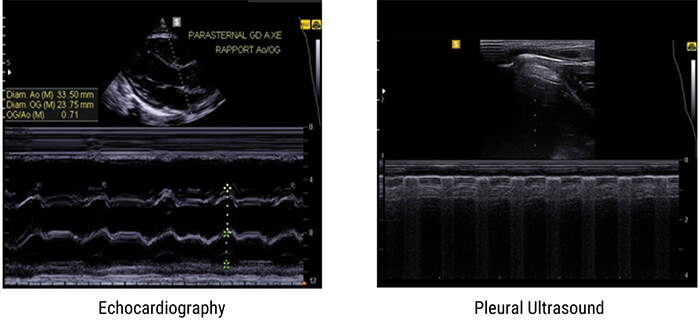

M-Mode

The M-Mode, or Motion Mode, is used to analyze moving body parts, and commonly used in cardiac and fetal cardiac imaging. It is based on the principle of recording the amplitude and rate of motion in real-time, by continually measuring the distance of the object from the single transducer at a given moment. The single sound beam is transmitted, and the reflected echoes are displayed as dots of varying intensities, thus creating lines across the screen.

The M-Mode (Motion Mode) is and commonly used in cardiography, where the direction of the beam is fixed and the returned echoes are recorded as a function of time.

Previously, we mentioned that the M-Mode is a unidirectional examination mode, that allows the analysis of tissue movement. This mode of representation is obtained by scrolling successive ultrasound signals corresponding to the same direction of the beam on a video monitor. The amplitude of the signal is coded in gray level, and useful in echocardiography for the analysis of heart valve movements.

Examples of Images

Here are some examples of M-Mode images, where the motion of the body part being scanned is displayed along the horizontal axis.